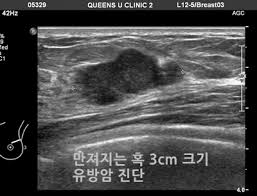

정기적인 유방 촬영술(맘모그램)과 초음파 검사는 유방암 진단에 필수적입니다. 특히, 고위험군 여성은 40세 이전에도 정기 검진을 시작해야 합니다.

의사가 유방의 덩어리를 발견할 경우, 생검을 통해 조직 샘플을 채취하여 암세포의 유무를 확인합니다.